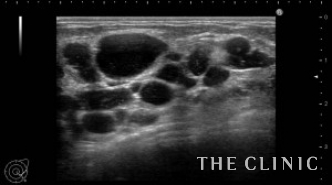

この方は5年前から数回に分けてヒアルロン酸注入を受けられています。通常、ヒアルロン酸は2年程で吸収されていきますが、この方は数回に分けて何度も注入されているため炎症が起こりヒアルロン酸の周囲に被膜を形成してしこりになっていました。エコーにて確認すると、数ミリのものもあります。注入部位も通常であれば乳腺下ですが、この方はバラバラに注入されていて皮下・乳腺内・乳腺下・大胸筋内と様々な層にあり、難易度は最高レベルでした。(右側の画像:ヒアルロン酸が蜂の巣の様に隔壁を作りしこりになっている)